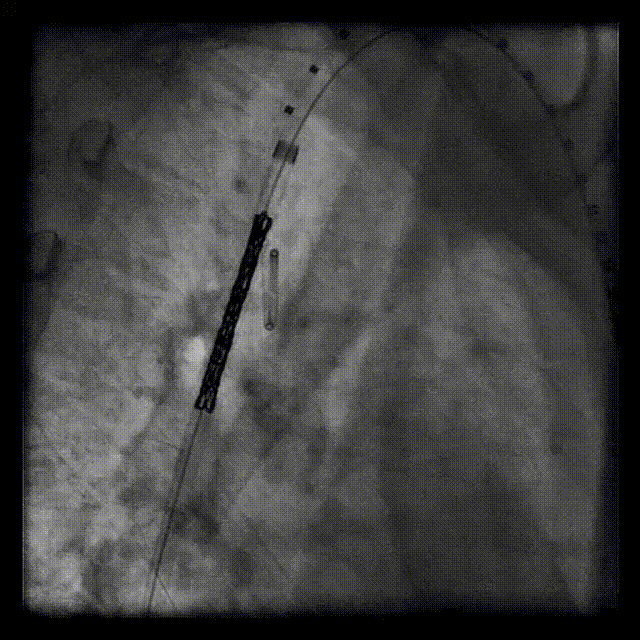

关键步骤:穿通闭塞离断部位。股动脉逆行途径将6F长鞘头端送至降主动脉离断起始部,5F MPA导管及泥鳅导丝经长鞘至离断端,长鞘支撑下,泥鳅导丝配合MPA导管轻柔操作,反复尝试,将260cm0.032‘Terumo软泥鳅导丝和5FrMPA导管逆行穿通闭塞离断部位至左锁骨下动脉。

导丝逆行通过弓离断处